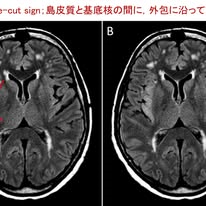

・Insular knife-cut signはヘルペス脳炎早期診断の切り札となるか?

**岐阜大学医学部下畑先生の2025年9月5日のFB投稿です**

ヘルペス脳炎は臨床的に重要なウイルス性脳炎であり,発症から治療開始までの時間が予後を大きく左右します.しかし,症状や検査所見は非特異的で,確定診断に用いられる脳脊髄液PCRも約5%で偽陰性を示すことが知られています.このため,臨床現場では「いかに早くヘルペス脳炎を疑い,治療を開始できるか」が大きな課題となっています.

今回紹介するイタリアからの研究は,ヘルペス脳炎の診断を強く指示するMRI所見「Insular knife-cut sign」に注目したものです.これは,FLAIR画像の軸位断で,島皮質に広がる異常信号と基底核の間に,外包に沿って鋭いナイフで切り裂かれたような境界を認める所見です.下図では,赤線で外包に沿った境界が示され,島皮質の異常信号が基底核に及ぶことなく明瞭な境界を示していることが分かります.またFLAIR画像で確認できず,他の撮像系列(例:拡散強調像や造影T1強調像)のみで認められる異常は除外されます.

今回,ご紹介するのはイタリアの3施設で行われた後方視的研究で,ヘルペス脳炎疑い188例が検討されました.うち44例がヘルペス脳炎と診断され,144例は自己免疫性脳炎,クロイツフェルト・ヤコプ病,腫瘍,感染性脳炎などの他疾患でした.結果として,Insular knife-cut signはヘルペス脳炎の52.3%に認められたのに対し,他疾患ではわずか0.7%のみで,特異度は99.3%と非常に高いことが示されました.さらにMRIの再検査を含めると感度は70.5%に上昇しました.多変量解析ではこのサインが最も強力な独立予測因子であり,側頭極病変や脳脊髄液細胞増加を凌駕する診断的価値を持つことが明らかになりました.

臨床の現場で重要なのは,この所見が「PCR陰性例」や「腰椎穿刺が禁忌の症例」でも診断を支持する手掛かりとなり得る点です.また,結果が出るまで数日を要するPCR検査に先立って診断的裏付けを与え,抗ウイルス薬投与の継続判断に資する点も見逃せません.一方で,このサインを認めない症例も存在するため,サイン陰性をもってヘルペス脳炎を否定すべきではなく,臨床的疑いがあれば即座に治療を開始する原則は変わりません.

以上より,Insular knife-cut signは,ヘルペス脳炎診断における新たな切り札といえるMRI所見のようです.今後,診療現場でこの所見が広く知られることにより,より迅速で適切な診断と治療につながることが期待されます.

Marini S, et al. Diagnostic Value of the “Insular Knife‐Cut” Sign in Patients With Suspected Herpes Simplex Virus Encephalitis. Eur J Neurol. 2025;32:e70152.(doi.org/10.1111/ene.70152)